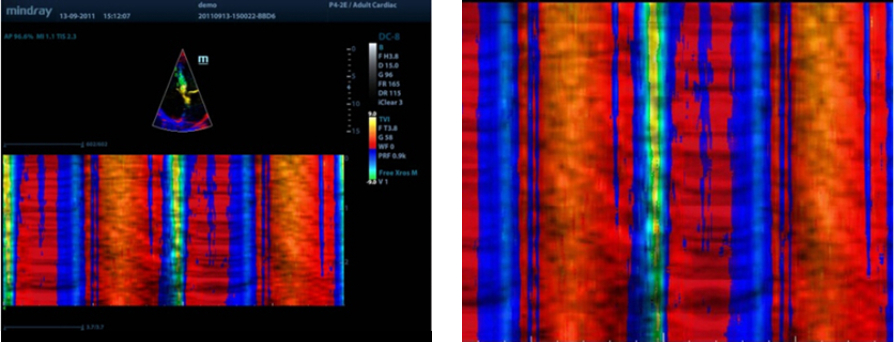

Free Xros CM?

Secara akurat menilai gerakan miokardial pada berbagai tahapan, dan sekaligus menentukan sinkronisasi miokardial. Laju bingkai yang tinggi memberi Anda hasil yang akurat:

TDI

Tissue Doppler Imaging memungkinkan Anda secara kuantitatif menilai fungsi dan gerakan miokardial lokal, sehingga memberikan mode TDI lengkap agar diagnosis lebih cepat dan langsung.